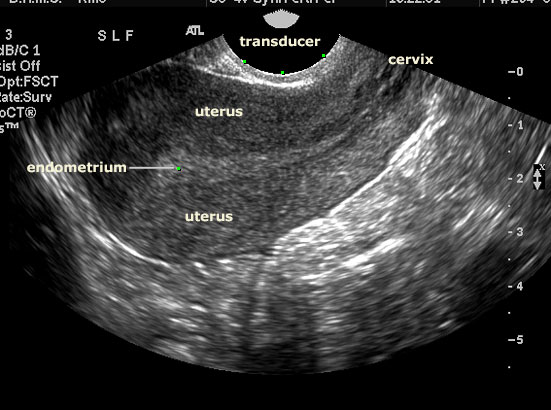

She proceeded to move it across my lower abdomen, pressing harder here and there, angling it, all the while pressing different buttons on the machine. I couldn’t read her face for clues. Like other doctors and technicians, she mastered the poker face. I did see a small furrow between her eyebrows here and there. Each time, I would look at the monitor but all I saw were grey smudges. How could they tell anything from this?

I entered a room with a desk that wrapped around three walls upon which sat three large monitors. All lit up with black and white smudges.

He then proceeded to explain that the uterus picked up the tracer because it was a muscle and that while there were some changes due to the anti-cancer drug I was taking, those changes were normal and I had nothing to worry about. He told me I had some cysts on the ovaries but that they were very common and come and go frequently.